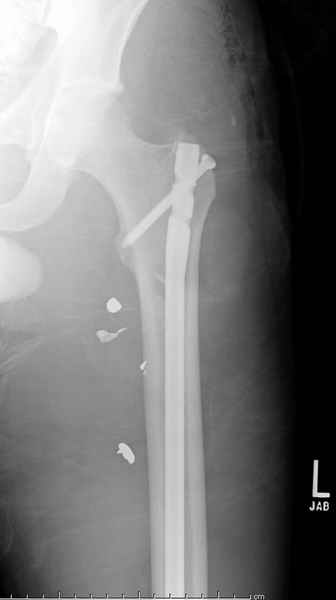

Больной с огнестрельным переломом бедра с вовлечением около 15% медиального кортекса, входное отверстие около 1 см в диаметре; стабильный, без сосудистых и неврологических признаков.

Входные маленькие отверстия от ранении просто игнорируются, никаких дренажей, как любое колотое ранения, они закрываются и были случаи через месяц. Конечно, ведется профилактика открытых ранении: сыворотки и т.д., но еще самое главное уделяем профилактике образования перелома из-за стресса в результате дефекта кортикального слоя.

Литературные данные о влиянии кортикального дефекта на стрессовые переломы в длинных трубчатых костях в основном встречаются в онкологии, например кортикальный дефект более 50% имеет больше шанса стрессовых переломов, чем в нашем случае.

Учитывая, что больной получил травму не во время визита в церковь, и он является одним из представителем 40 миллионного “outstanding itizen”, без медицинской страховки, без работы в свои 39 лет, и без надлежающей ортопедической дисциплины у которого отсутсвует страх стрессового перелома, было рекомендовано оперативное лечение: профилактическое антеградное интрамедуллярное штифтование.

Методика штифтования при отсутствии большой зоны перелома как при онкологических профилактических штифтованиях, расверливание интрамедуллярного канала проводим с предварительным наложением дополнительного дренажного отверстия в дистальном отделе бедра (в данном случаи в канале оставили 6.5 мм канюлированный шуруп), иначе при создании давления в канале во время сверления имеется опасность эмболизации легочной артерии тромбом.